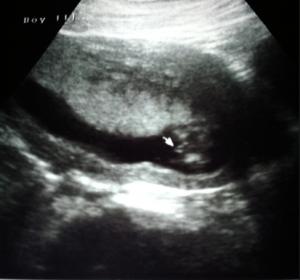

14weeks 5days What do you think? :)

I know that 14 weeks is early to do a gender determination test! But my boyfriend and I were very excited to find out so we went to see anyways!

We were told boy which is awesome!!! But since we did it so early I wanted to post some pictures and see if anyone had similar photos or just wanted to let us know what they think! After coming home and doing some research and comparing of ultrasounds, I read that a lot of times you can't tell at this period because the boy and girl parts look very similar. Let us know what you think! Either way we are very blessed!